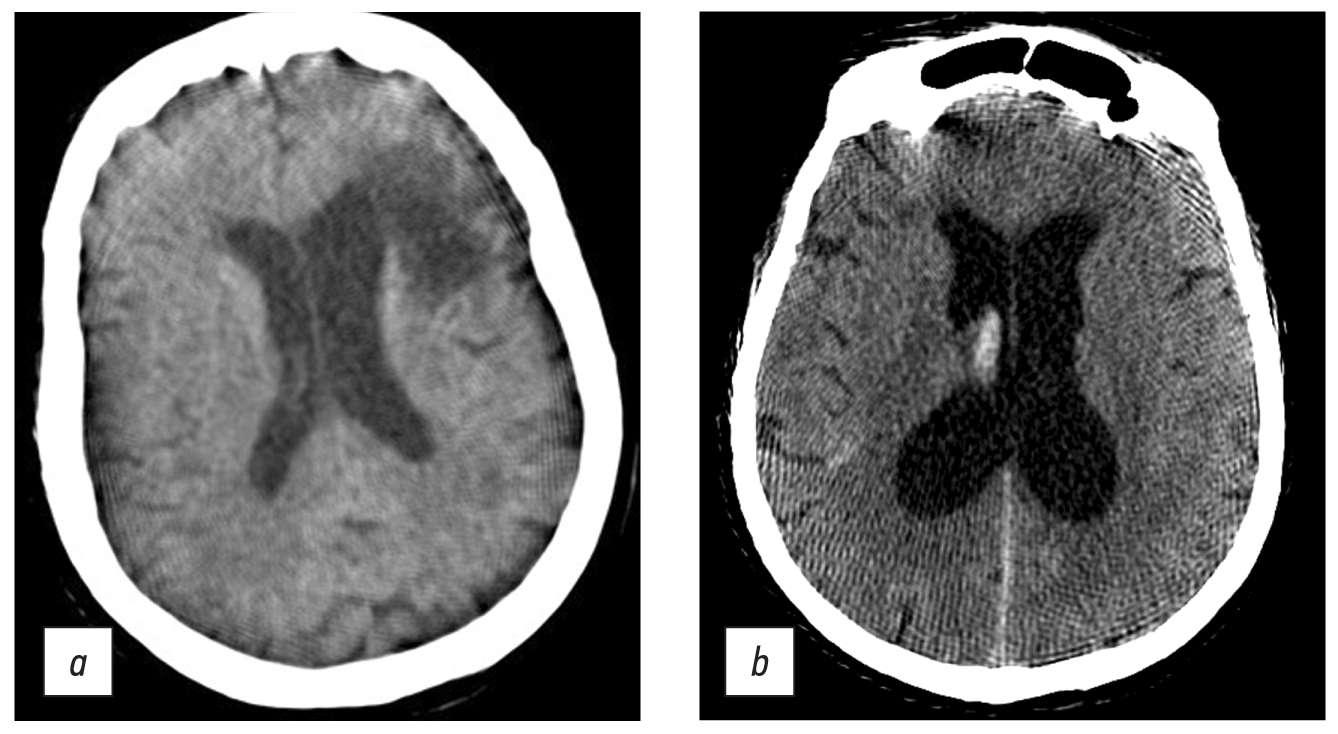

Brain CT was used to diagnose acute cerebrovascular accident, intracranial hematomas, brain tumors, and traumatic skull injuries (Fig. 7).

Fig. 7. Axial computed tomographic images of the brain: (a) reconstruction of a 3-mm low-density area at the anterior horn of the left lateral ventricle, in the periventricular, subcortical direction (CT image of subacute cerebrovascular accident of the left middle cerebral artery), and (b) a 1-mm site of subarachnoid hemorrhage with blood breakthrough into the ventricular system (vicarious hydrocephalus).

Windmill artifacts (Fig. 8a) were mixed with strike artifacts and helical scanning [5], and artifacts intensified at the level of skull base, where significant beam hardening and scattering artifacts occurred (Fig. 8, b). Therefore, subtentorial brain areas were challenging to assess.

Fig. 8. Axial (a) and sagittal (b) computed tomographic images of the head in the region of the posterior cranial fossa and base of skull showed windmill, strike, beam hardening, and scattering artifacts. Area of bone structures and the posterior fossa is hard to evaluate.